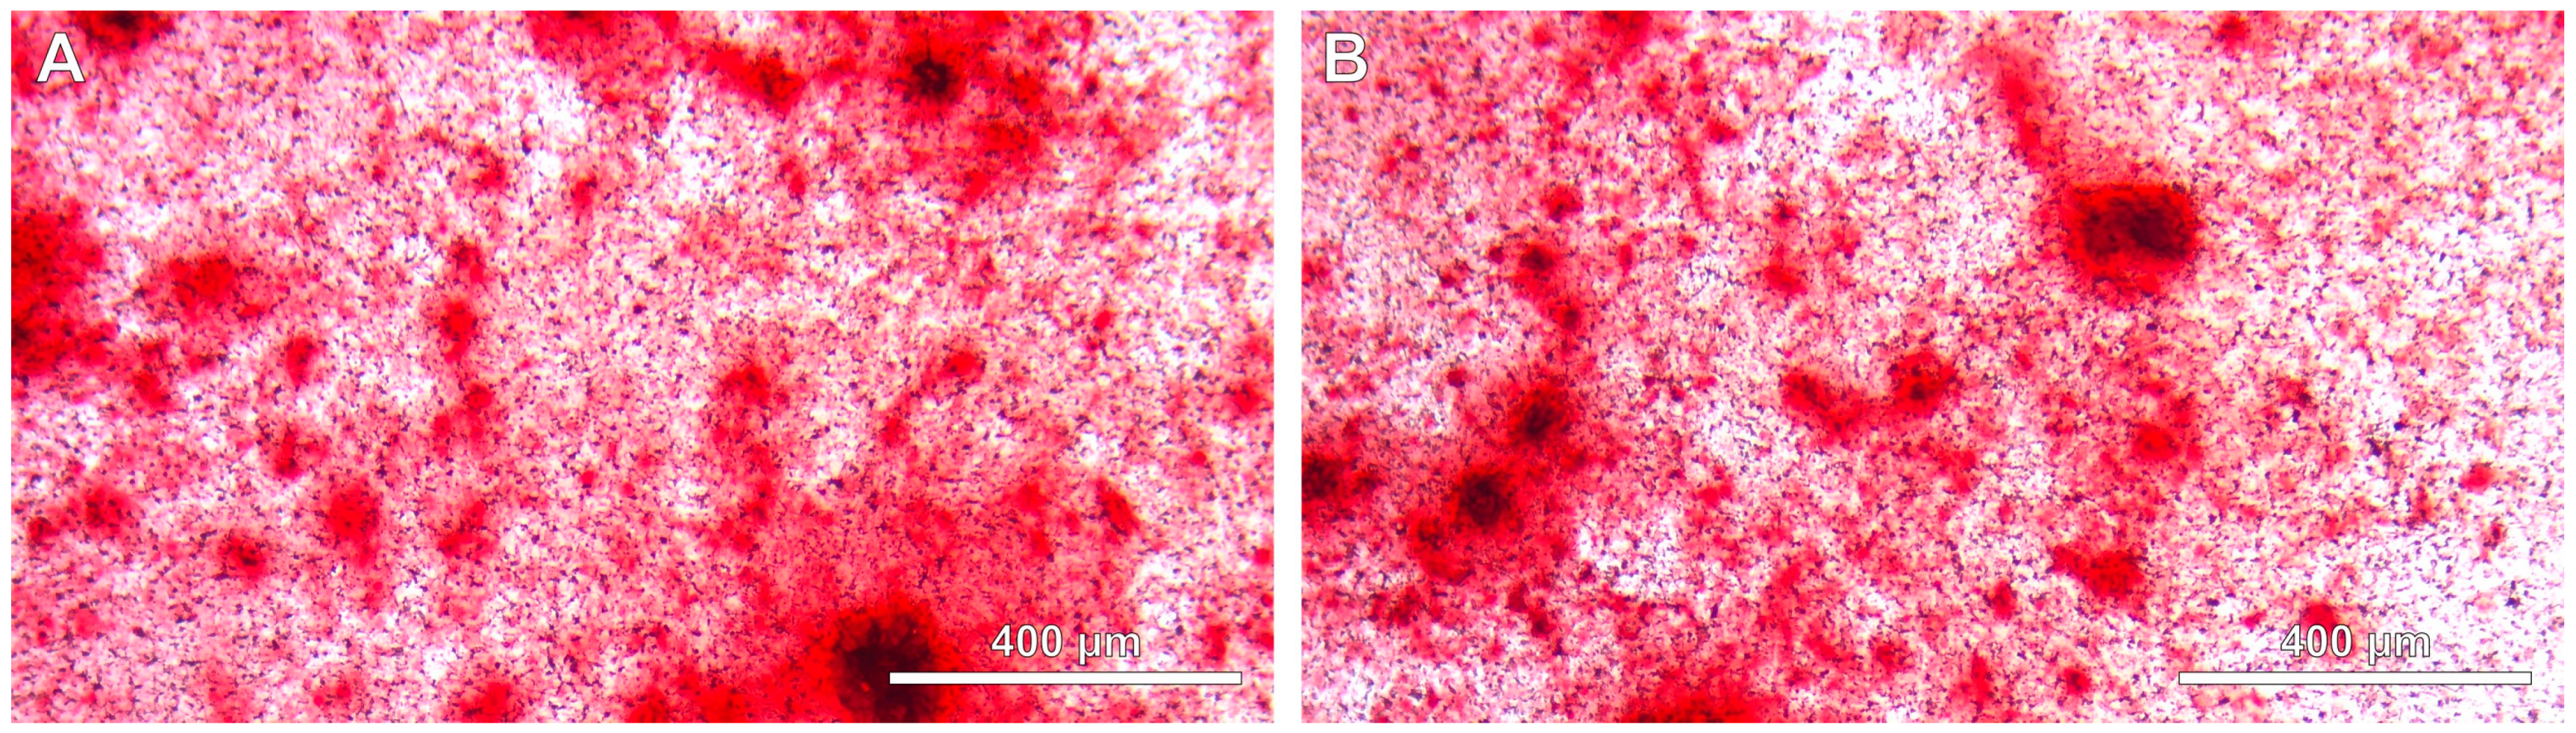

3.4. The Influence of DSCs Differentiation